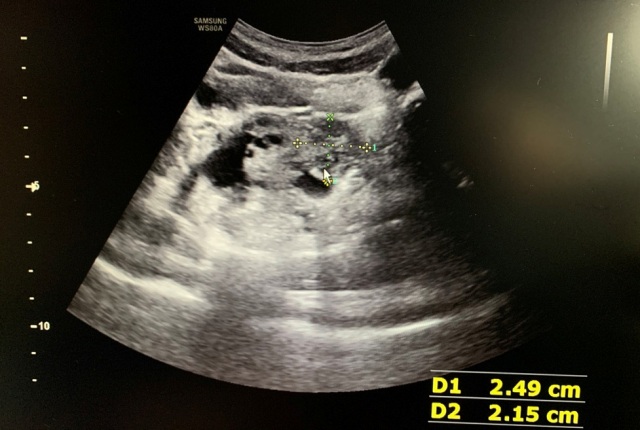

儿科医生接诊后,发现患儿脸色苍白、表情痛苦,查体得出脐周及左下腹压痛,且左下腹压痛明显。凭借多年的诊疗经验,儿科医生觉得患儿的腹痛与平常小孩的腹痛不太一样,再次追问病史得知,患儿曾于2020年因“卵巢扭转”在省儿保行右侧附件切除术,医生怀疑患儿是左侧卵巢扭转,立即进行子宫、附件B超及相关检查。B超医生反映情况有些异样,儿科医生高度怀疑左侧卵巢扭转,建议立即转诊至省儿保就诊。省儿保B超考虑左侧卵巢扭转,立即急诊手术复位。